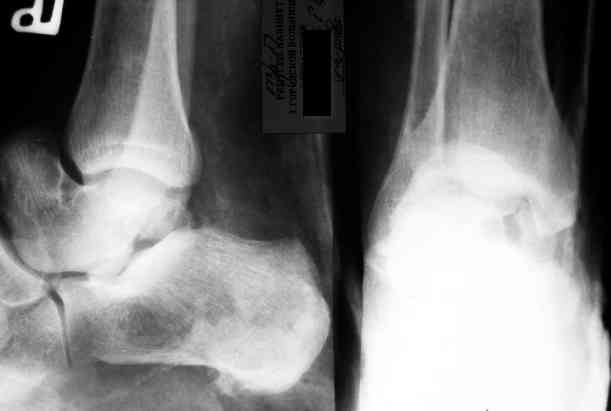

Re: Редкое повреждение - полный вывих тарана!

Уважаемый Александр! Как обещал представляю Р-граммы и операционные фото.